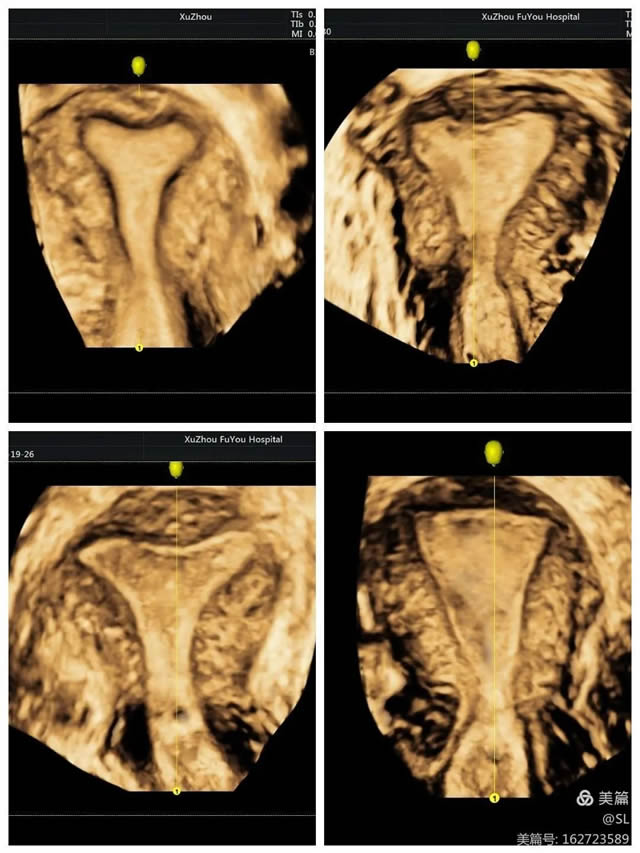

立體成像(xiàng)安全(quán)無創

據張麗(lì)主任介紹,經(jīng)陰道三維彩超是使用容積探頭對宮腔內的病變及盆腔進行三維成像,可多模(mó)式重建成像,全方位、多視角完整、立體顯示宮腔內部結構和空間位置關係(xì),直觀清晰的立體(tǐ)成像對婦科疾病的診斷更加(jiā)準確,在婦科檢查中得到廣泛應用。

先天(tiān)性子宮畸形是婦科(kē)的(de)常見疾病,也是女性不孕不(bú)育、習慣(guàn)性流(liú)產、胎兒宮內發育遲緩等疾(jí)病(bìng)的主要原因之一。經陰道三維彩超在(zài)評估子宮病變等(děng)方麵,提供了更豐富的影像信息。這種超聲技術不僅能夠更好(hǎo)的觀(guān)察子宮外形輪廓(kuò)及宮腔內膜的形態,還能清晰觀察患者宮腔內的可疑部(bù)位和周圍組織,幫助醫生更(gèng)準(zhǔn)確的分析判斷病情。

張麗(lì)主任提到,經陰道三維超聲是在二維(wéi)超聲基礎上技術升級的(de)檢查手段。二維超聲是斷(duàn)層掃查,很難顯示冠狀切麵,三維超(chāo)聲可以立體實時、從多個麵來觀察,提供比二維超聲(shēng)更豐富的(de)信息(xī)量,因此醫生根據三(sān)維彩超來診斷,結果會更加準確。